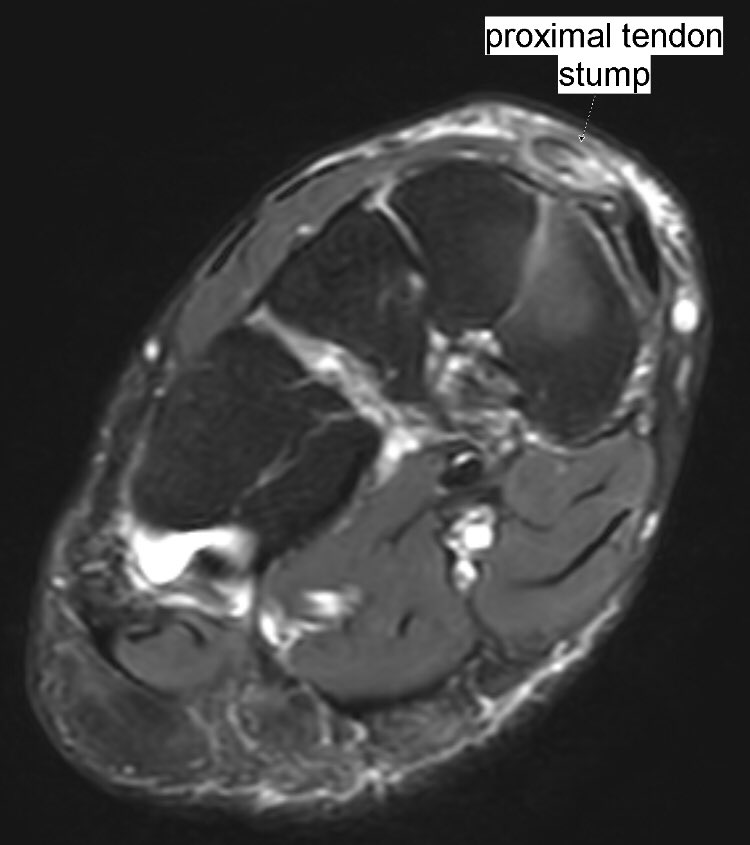

Extensor hallucis longus (EHL) tendon closed full-thickness tear: fluid inside tendon sheath, abrupt EHL tendon fibers complete discontinuity with a 4-cm gap, tendinopathy of both stumps. Mechanical impingement by bone spurs.

#MSKrad#foot#orthopaedicspic.twitter.com/h9LcB2Pgjp